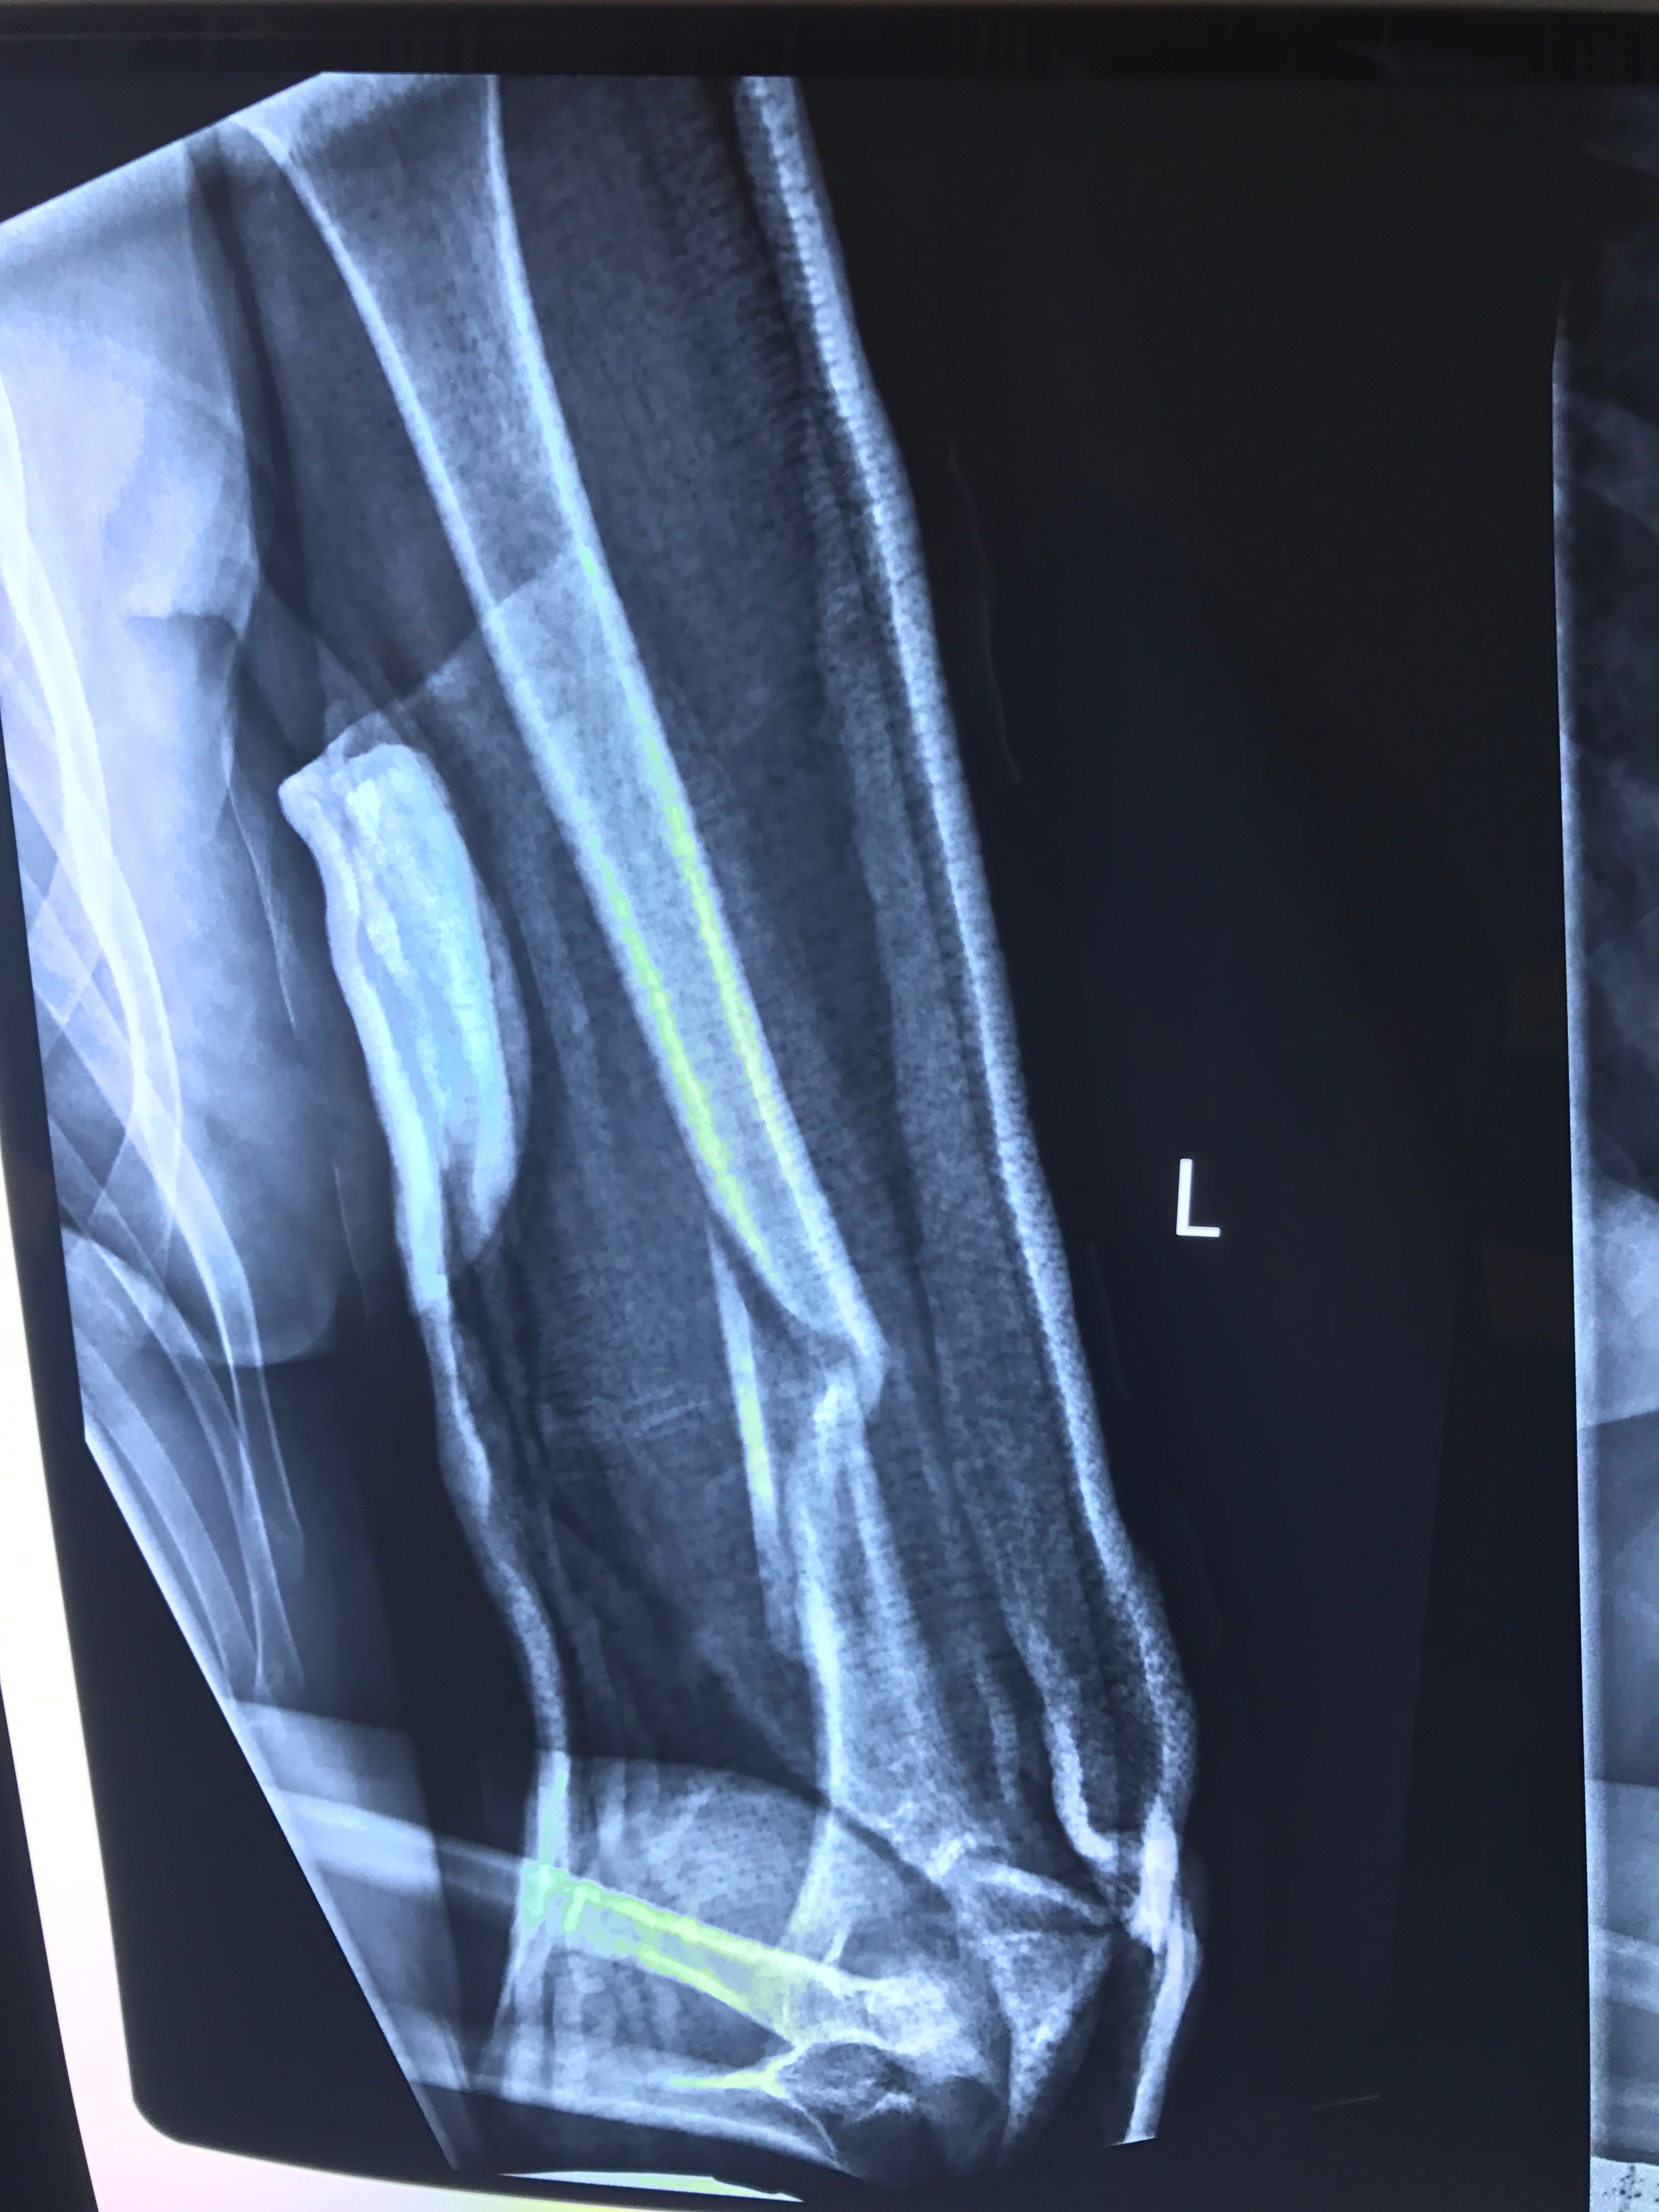

From www.orthobullets.com

Humeral Shaft Fractures Trauma Orthobullets How To Heal A Broken Humerus How should it be treated? the humerus is the upper arm’s only bone. a humerus shaft fracture may be treated with or without surgery, depending on the fracture pattern and associated injuries (i.e., nerve injury or open fracture). To manage your pain, we advise that. A fracture of the proximal part means that it is broken up near. How To Heal A Broken Humerus.

Clinical example of humerus fracture healing. Download Scientific Diagram How To Heal A Broken Humerus During this time, you will do. a humerus shaft fracture may be treated with or without surgery, depending on the fracture pattern and associated injuries (i.e., nerve injury or open fracture). Most broken shoulders can be treated without surgery. To manage your pain, we advise that. It connects the shoulder to the elbow and is strong enough that breaking. How To Heal A Broken Humerus.

From drcetinisik.com

Humerus fracture; From diagnosis to treatment Dr. What's wrong with you? How To Heal A Broken Humerus Some people can recover without surgery and only need a. the humerus is the upper arm’s only bone. if you break your humerus, you might need surgery to repair your bone. These fractures normally take between 6 to 12 weeks to heal. During this time, you will do. a humerus shaft fracture may be treated with or. How To Heal A Broken Humerus.